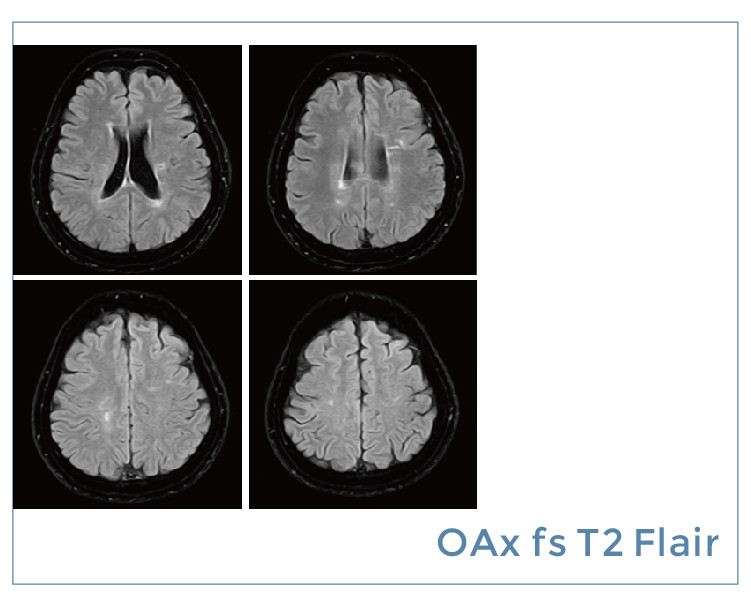

【朗润影像档案】20190823磁共振影像病例结果讨论